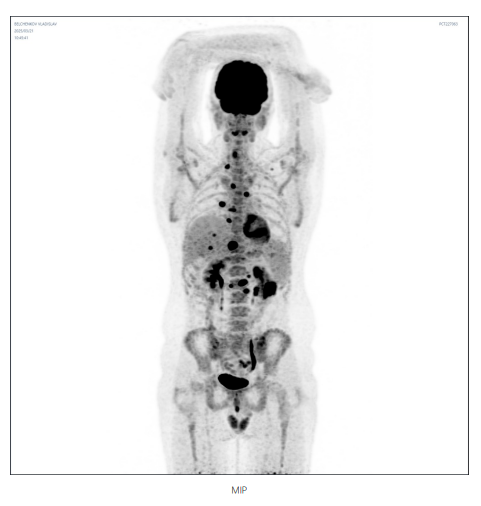

2025 年 3 月 20 日,弗拉迪斯拉夫在陆道培医院国际部工作人员的协调下入住北京陆道培医院。入院后,陆道培医疗淋巴瘤•骨髓瘤中心医生团队迅速为他进行了全面检查,骨穿、腰穿未见明显异常,但 PET/CT 显示纵膈、横隔上下多组淋巴结、肝脏及左肾多发结节,病灶较前增大,代谢较前增高,病情依然严峻。

在肿瘤负荷控制到理想状态后,4 月 14 日开始进行 FC 方案预处理,为 CAR-T 细胞回输做准备。回输后针对性应用 PD-1 单抗增强 CART 扩增和疗效。令人惊喜的是,整个治疗过程仅出现 1 级细胞因子风暴(CRS),未发生神经毒性反应。2025 年 5 月复查 PET-CT 显示所有病灶代谢完全消退,Deauville 评分 1 分。这一结果令患者和家属欣喜若狂,也标志着此次治疗取得了阶段性的巨大成功。